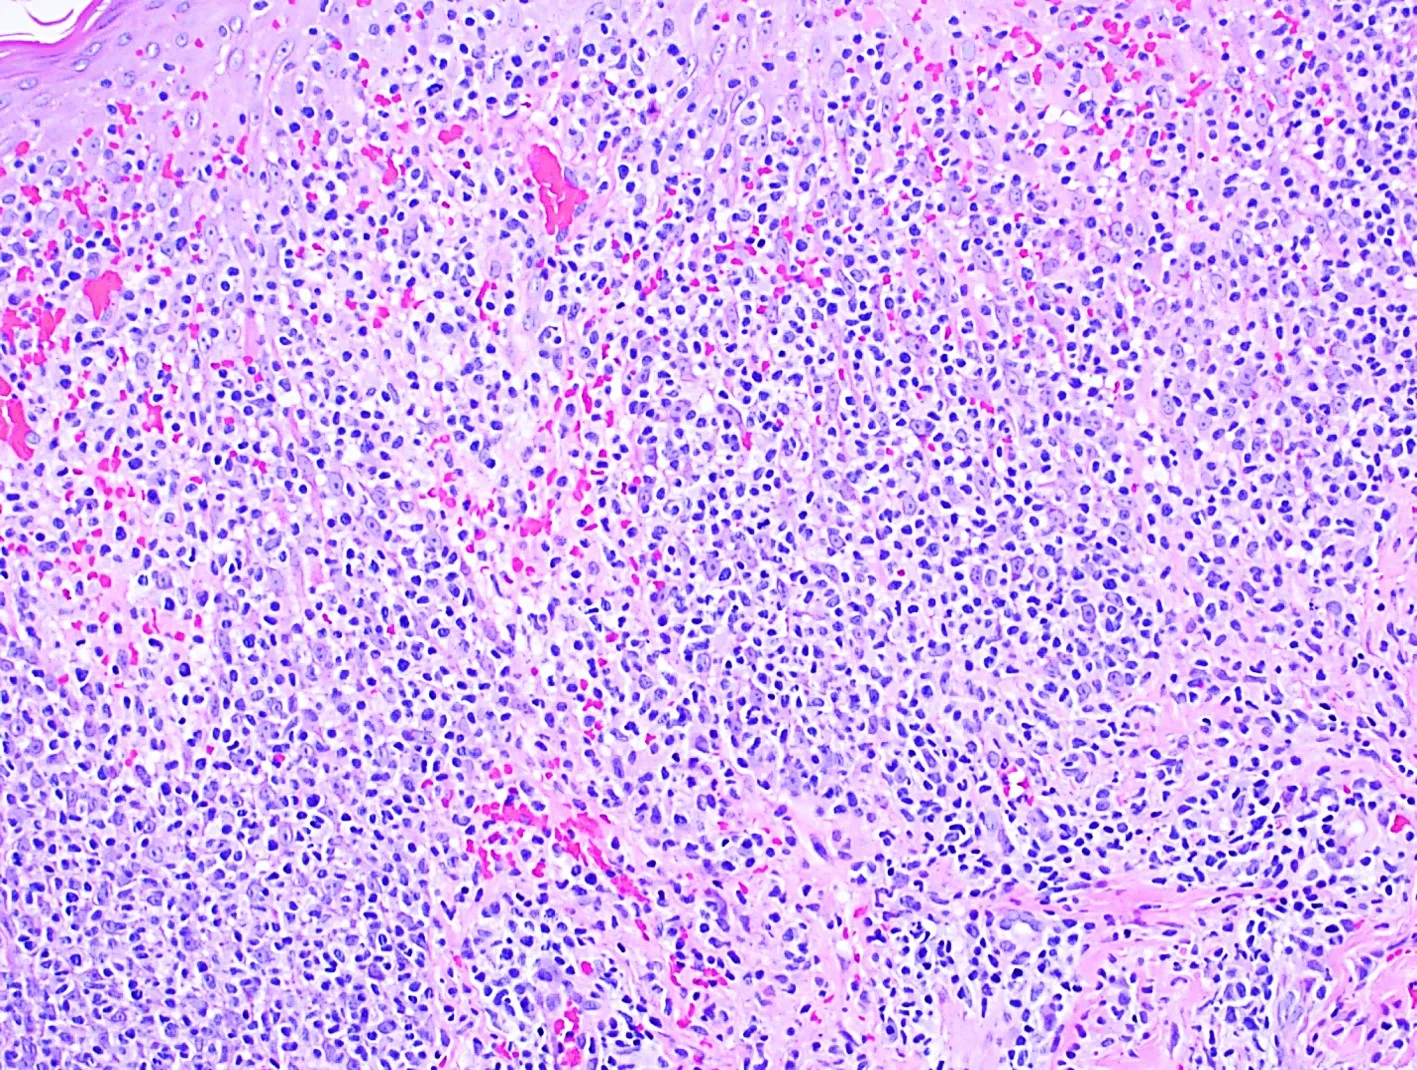

Case 19: Massive Localized Edema of the Vulva Mimicking a Neoplasm

History: A 38-year-old, morbidly obese female was referred for an oncology consultation due to massive enlargement of the vulvar region. The enlargement was first noticed by the patient 6 years ago, and since onset, had doubled in size. The lesion was occasionally painful and limited sexual activity. Her past medical history included hypertension, endometriosis, and a cervical excision procedure at age 18 for an abnormal pap smear. Familial cancer history included lung cancer in both an uncle and a grandfather and pancreatic cancer in her grandmother.

Physical Examination: A massively enlarged, verrucous/plaque-like lesion with multiple, small coalescing polypoid masses were seen encompassing the vulvar area. The lesions extended down to the anus. Similar but smaller plaques were also noted on the labia majora. The mons pubis contained a separate, 8 x 12 cm, firm but mobile, pedunculated mass.

Histopathology: Papillomatosis, hyperkeratosis, and dermal fibroplasia with dilated lymphatics in a circumscriptive pattern was observed. There was no evidence of malignancy.

Diagnosis: Massive localized edema of the vulva

Points of Emphasis: Massive localized lymphedema of the vulva is a rare, “pseudosarcoma” associated with obesity, immobilization, prior surgery, and blunt trauma. It is characterized by prominent expansion of the vulvar connective tissue leading to massive, pedunculated masses and verrucous, plaque-like lesions of the skin. These lesions can mimic cancers such as lymphangiosarcoma. Although rare, this is an important entity to recognize due to its gross similarities to a neoplasm. In addition, because a significant proportion of angiosarcomas can arise in the setting of chronic lymphedema, close follow-up is recommended in these cases.